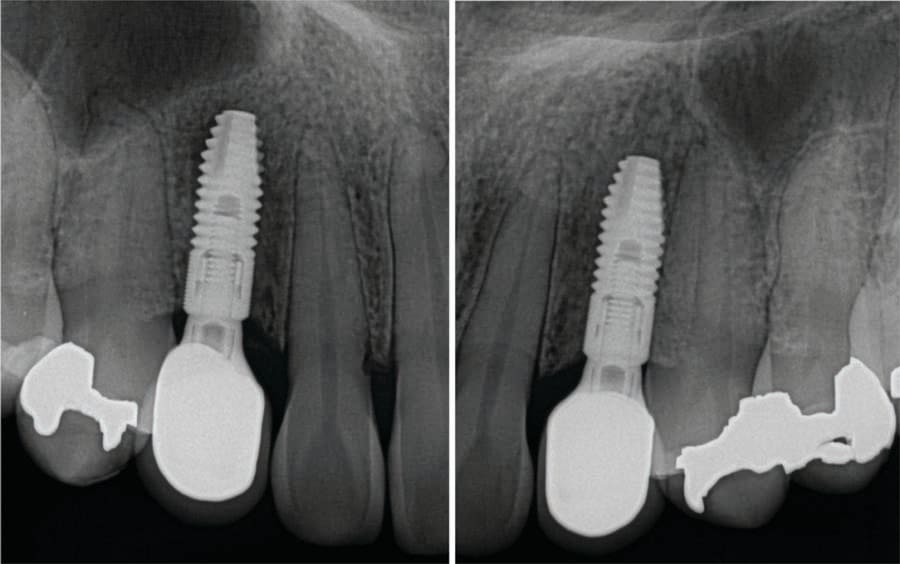

At 3 months post implant placement the patient returned to initiate restoration of the implants. A CBCT was taken to check bone levels on the integrated implants. Panoramic and occlusal views were analyzed verifying the implants in contact with the surrounding bone and appeared ready to restore (Figure 13 and Figure 14). Local anesthetic was administered, and the implants were uncovered with the Solea CO2 laser and the healing screws exposed (Figure 15). Healing abutments were placed in the implants and the patient scheduled for impressions.